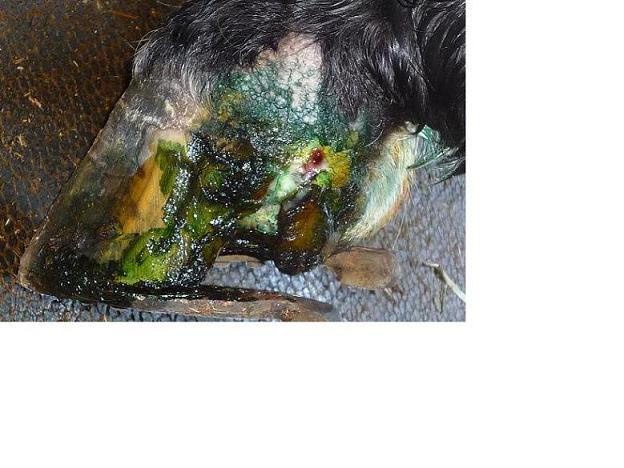

Posted on Friday, Mar 6, 2009 - 9:50 am:  The top picture is now, the bottom is before the new vet came out. When she came, she cut off everything below the crack because it turns out it was all just hanging. But that also removed some of his support which is why she thought that he needed the shoe. The top picture is now. |

Posted on Friday, Mar 6, 2009 - 12:58 pm: So, we just finished cold hosing it, let it dry and coated with Koppertox (that's the green in the pic) and I actually think that it looked a little better and definitely didn't seem to be oozing as much.I've scheduled an appt with an equine hospital, but they are 1.5 hours away. I'm really concerned about whether his good leg can withstand the stress of a ride that long. He's horrible to load when he's sound and I have no idea how we are going to get him on the trailer the way he is right now, but I'm trying to be positive. My gut really tells me that we need to remove that shoe before he tries riding in a trailer, but I really need some input here. I've called the young vet and he's willing to come out on Sunday afternoon to tranq him so that a farrier can remove the shoe and I've left a message for the farrier, but haven't heard back yet. I really feel like I'm offending my vet, and he's been SO wonderful about coming over here all the time and being here when we need him. I just feel so helpless here.